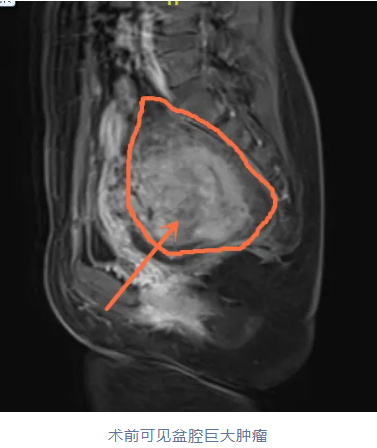

李女士很焦虑,经朋友介绍来到我院妇三科就诊,雷南香主任团队为患者进行仔细检查,经过三合诊,也就是经直肠、阴道、腹部联合检查,发现肿物位于子宫体中下段-宫颈后壁肌壁间/浆膜下,在阴道壁及直肠间,并向上延伸至骶前,边界清,大小约8.3×10.9×10.5cm,为盆腔腹膜后肿瘤,肿物被腹膜包裹,且被上方直肠乙状结肠遮盖,位置相当隐匿且罕见。

由于肿瘤较大且位置特殊,周围有重要神经和丰富血供,附近区域组织结构复杂,前方紧邻直肠壁,术中极易损伤导致不可控性大出血,手术难度大。

为了减少手术创伤,保全肿瘤邻近神经器官功能,妇三科联合胃肠外一科、影像中心、麻醉科等多学科专家制定了详细的手术方案,为患者实施腹腔镜下盆腔腹膜后肿瘤切除术。手术历时2小时,完整切除肿物,术中出血量控制在200ml以内,直肠壁及输尿管、盆底神经得到良好保护,术后病理提示为子宫平滑肌瘤。